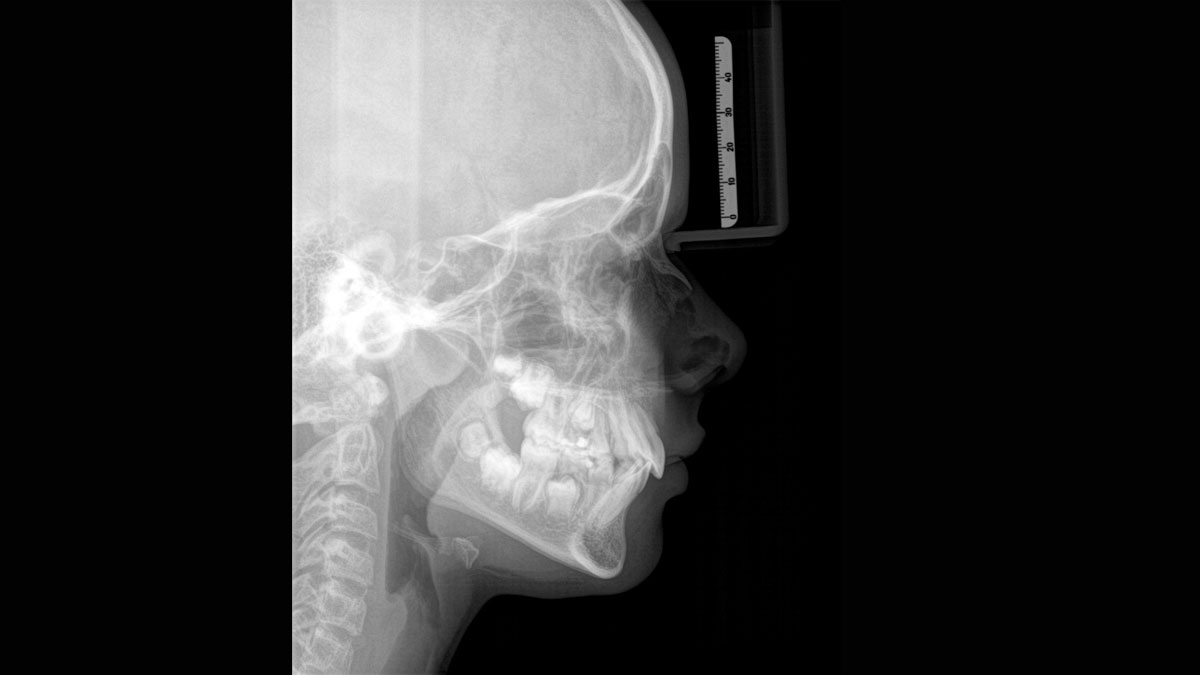

The high-quality 2D/3D X-ray device with a comprehensive range of services for every practice. Whether as a pure 2D device or including a 3D module – the Orthophos S is a reliable partner and optimized for everyday tasks. Its CsI Plus sensor with autofocus function ensures clear images, even in anatomically difficult cases. The automatic patient positioning together with the patented occlusal bite block enables an easy and timesaving patient positioning. For use in orthodontics, the Orthophos S is also available with an optional ceph arm. And because future-proofing is important to Dentsply Sirona, the cephalometric arm can be retrofitted at any time.

The ceph arm can be added on the right or left side of the unit and ordered at the time of purchase or retrofitted at any time